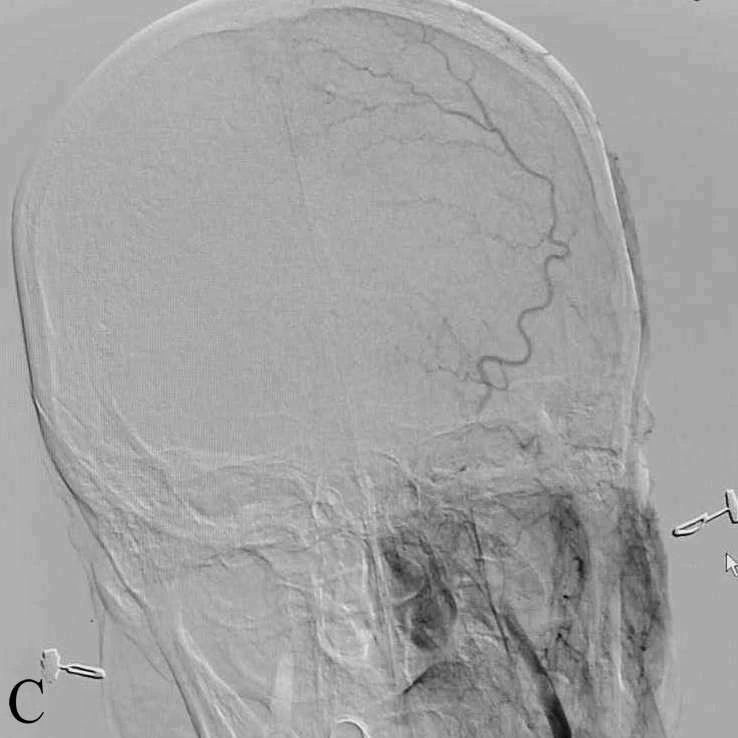

C:球囊导引导管+中间导管+支架取栓

D:取栓后右侧ICA造影正位示mTICI2b级再通